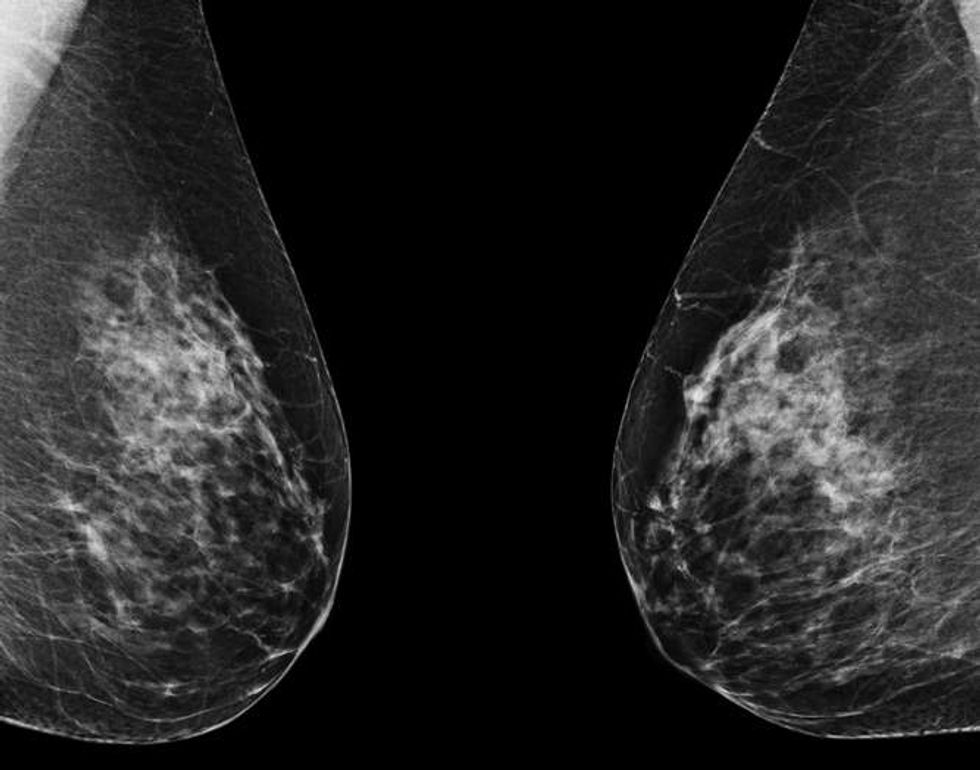

In June 2025, the FDA granted De Novo authorization (meaning the first of its kind) to Clairity Breast, the first AI tool cleared to predict a woman’s risk of developing breast cancer within five years using only a standard mammogram. Unlike traditional risk models that rely on age, family history or self-reported questionnaires, Clairity Breast analyzes the mammogram itself.

Clairity’s AI scans the images for subtle features in breast tissue that are invisible to the human eye or not yet recognized by medicine as warning signs. These patterns can reveal a woman’s likelihood of developing breast cancer even when her mammogram appears normal. The result is a validated five-year risk score that can help healthcare providers (HCPs) offer personalized follow-up care, such as earlier screening, preventive medications or genetic counseling, before any sign of disease is visible.